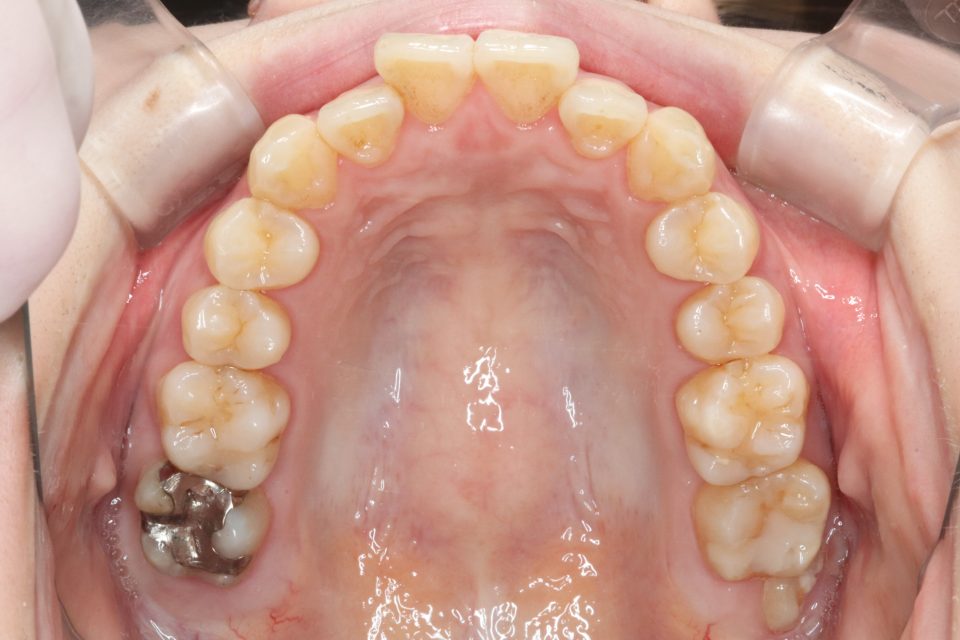

矯正治療前

20代女性です。

上の前歯が2本出ているのが気になると当院に来院されました。

部分的な矯正を希望され、

奥歯の嚙み合わせにも大きな異常はなかったため、

取り外し可能なマウスピース矯正で治療をおこないました。

きれいに並びきるよう歯のやすりがけ(IPR)をしています。